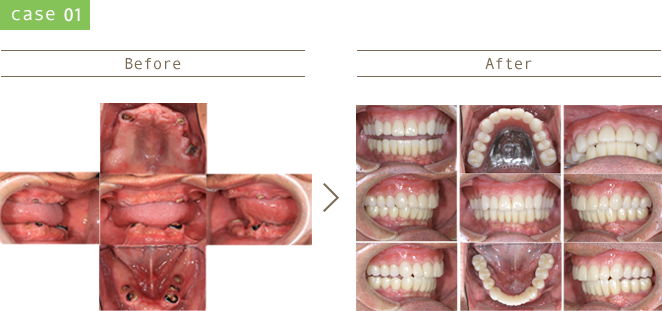

治療後20年・30年後を考え、患者さんが一生噛めることを目指した治療計画を心がけています。

審美的、骨格的、機能的、生態的な観点を包括的に鑑みて治療を行っています。

虫歯の再発リスクの少ない治療、歯周病の発症・進行を防ぐためのメンテナンスに注力しています。